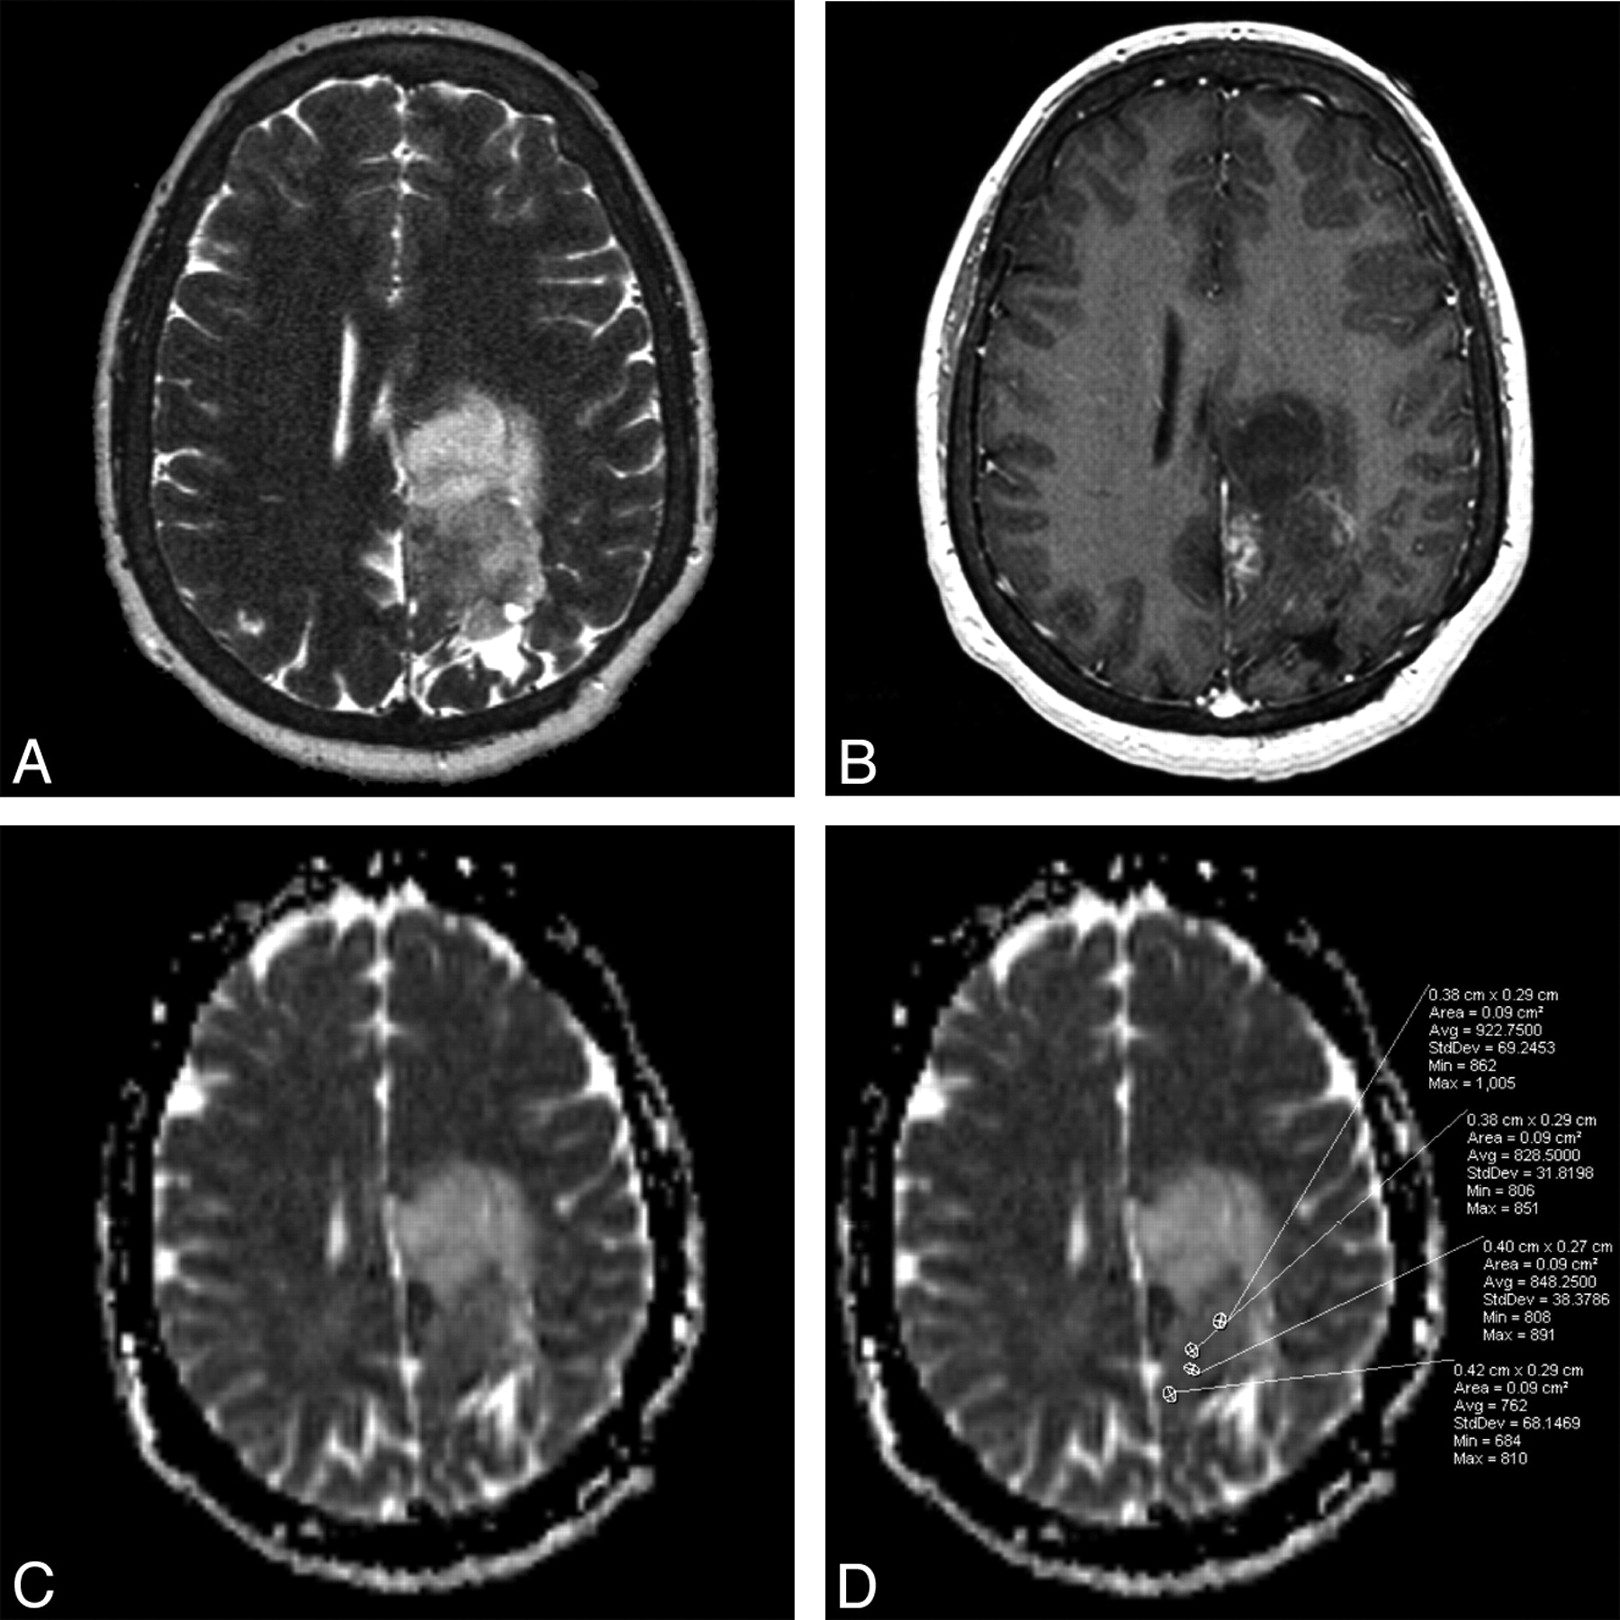

Grade III oligodendroglioma. A, Axial T2-weighted fast SE image shows a high-signal-intensity mass in left medial frontal and parietal lobes. B, Axial contrast-enhanced T1-weighted image shows minimal nodular post–contrast enhancement within the medial margin of the mass. C, Axial automated postprocessed ADC map shows low signal intensity along the posterior margin. D, As stated in “Materials and Methods,” 4 ROIs are placed in the areas visually assessed as the lowest in signal intensity on the ADC map. In this case, of the 4 ROIs, the lowest ADC value is 762 × 10−6 mm2/s, which was recorded for this grade III oligodendroglioma, below the 925 × 10−6 mm2/s threshold.

Tumors of grade III yielded lower ADC values, with a median ADC value of 1071 × 10−6 mm2/s (first quartile: 1000 × 10−6 mm2/s; third quartile: 1253 × 10−6 mm2/s) in grade II tumors and of 908 × 10−6 mm2/s (first quartile: 835 × 10−6 mm2/s; third quartile: 1021 × 10−6 mm2/s) in grade III tumors (Fig 2). ADC values were found to have relatively good predictive ability, with an area of 0.75 under the ROC curve. The optimal dichotomization cutoff value of ADC for classifying tumors as either grade II or III was identified as 925 × 10−6 mm2/s, with tumors with ADC values ≤ 925 × 10−6 mm2/s being deemed grade III, and those with >925 × 10−6 mm2/s, grade II. This classification rule for identifying grade III tumors resulted in a specificity of 89.1%, sensitivity of 62.1%, negative predictive value of 78.9%, positive predictive value of 78.3%, and accuracy of 78.7%. Furthermore, tumors with a low ADC value (ADC ≤ 925 × 10−6 mm2/s) were estimated to have odds of being of grade III 13.4 times greater than tumors with a high ADC value (ADC >925 × 10−6 mm2/s) (odds ratio = 13.4; 95% CI, 4.1–44.3; P < .001).